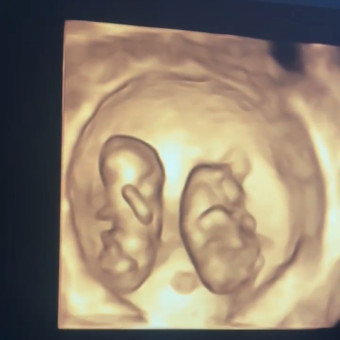

I will have 2 babies